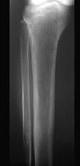

问题 下列哪项X线表现对甲状旁腺功能亢进症有诊断价值()

选项 A.弥漫性脱钙 B.纤维囊性骨炎 C.骨囊肿样变化 D.骨膜下皮质吸收、颅骨斑点状脱钙 E.多发性骨折或骨骼畸形

答案 D